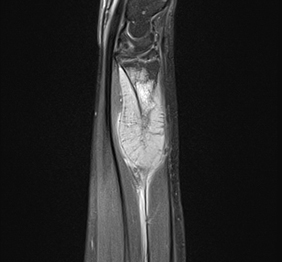

RMN osteo-articular

RMN-ul este esential in identificarea si evaluarea afectiunilor la nivel osos (tumori, osteonecroza, etc), precum si ale partilor moi (tumori, leziuni musculare, ruptura de ligamente, etc).